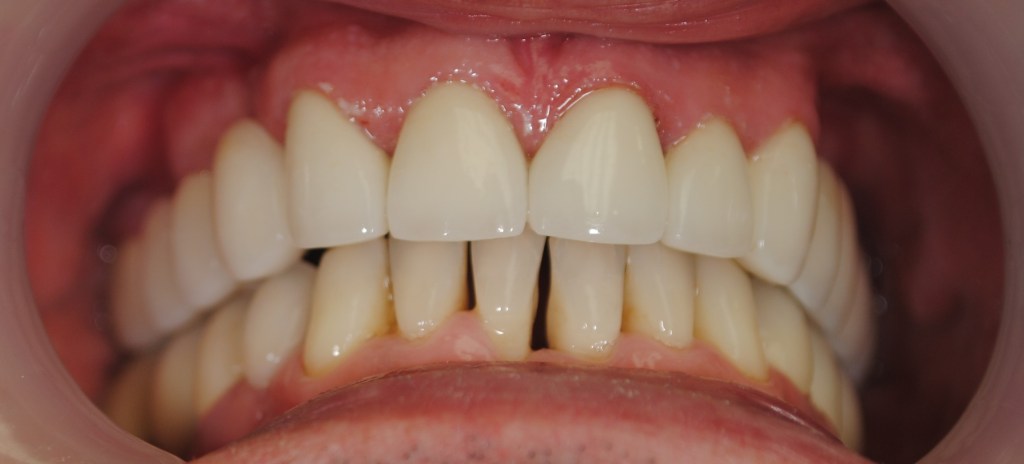

Kozmetikai és funkcionális kezelés: felső torlódott fogak kiegyenesítése, koronák enyhe kifele döntése, mélyharapás korrigálása.

A választott korona típusa: CAD/CAM (komputer vezérelt tervezés/megmunkálás) technológiával készült cirkónium (fémmentes) szóló koronák.

A választott fogszín: A2

A protetikai munka elkészülésének ideje: 5 munkanap.